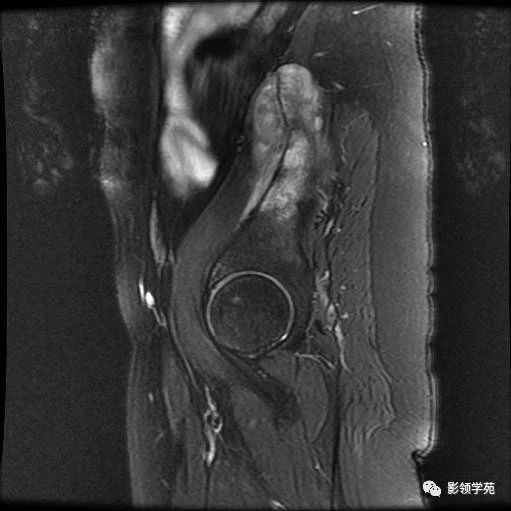

左髂部疼痛肿胀半年——恶性肿瘤 影领学苑 · 公众号 · · 5 年前 · |

椎管内囊性病变的分类和影像诊断 影领学苑 · 公众号 · · 5 年前 · |